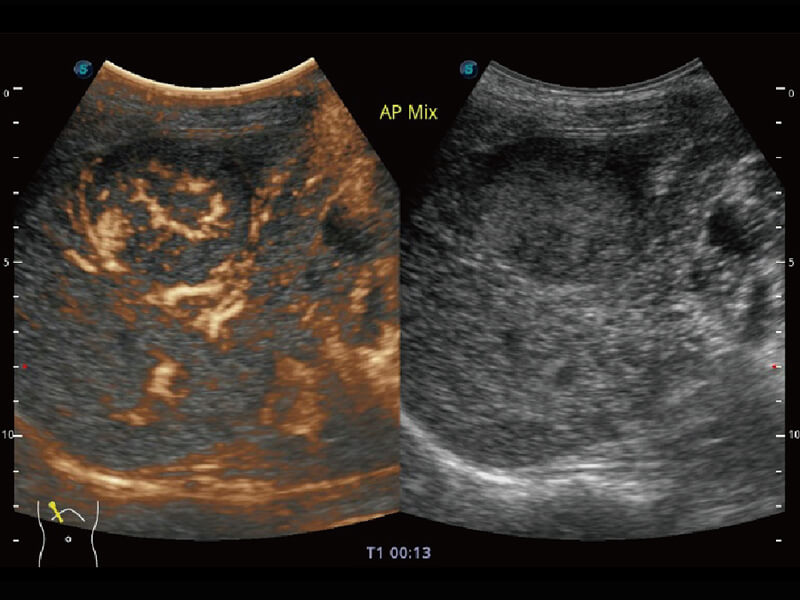

彩色多普勒超声诊断系统

S60探头工艺,从前端信号处理每一个环节采集无损声学数据,真实还原组织原貌,再现解剖细节。

超宽频带技术,为容积成像带来优质的二维图像基础,为您呈现丰富的结构细节,栩栩如生地展示宝宝的宫内形态以及各种组织的立体结构。